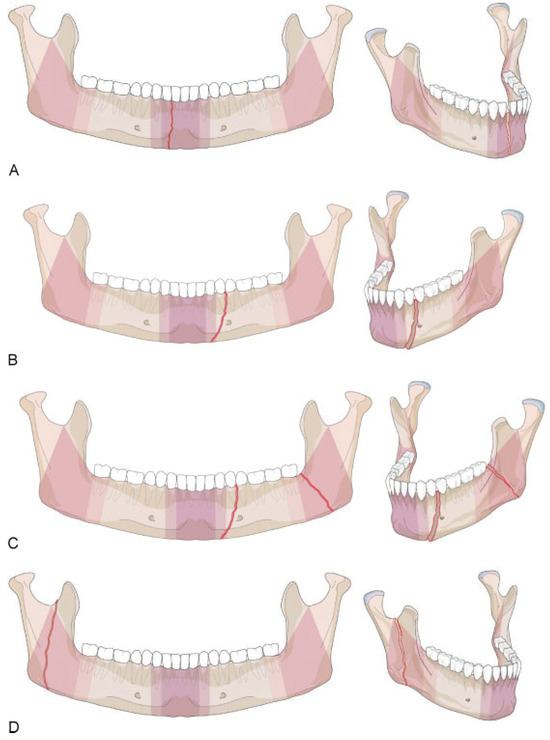

Symphysis/Parasymphysis Region

Mandibular Body Region

Angle/Ramus Region

Confinement—Fractures Located within Anatomical Regions

- • “Confined” fracture pattern: the fracture, irrespective of its morphology, remains within an anatomical region (including a transition zone) and does not extend into an adjoining region across a transition zone.

- • “Nonconfined” fracture pattern: the fracture crosses at least one transition zone and may extend over one or more adjoining region.

Appendix A. Additional level 2 coding examples of mandibular fractures